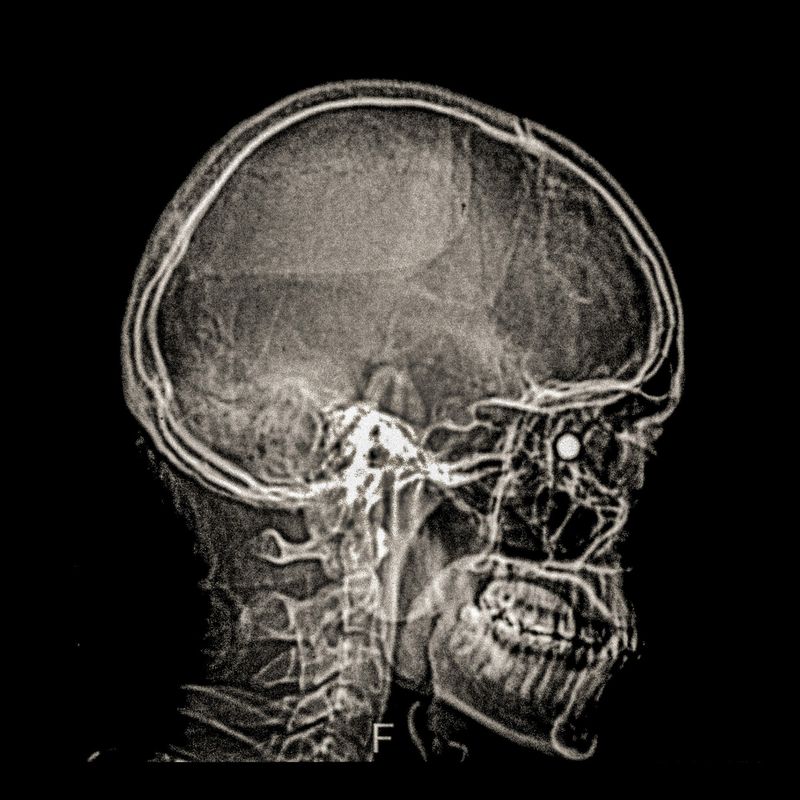

X-ray showing the pellet embedded in the skull of Ybar Soto (29) Ybar was hit by a pellet that lodged in his right eye on October 24, 2019 in Plaza Italia. Santiago. His diagnosis was ocular burst. Santiago, Chile. December 28, 2019